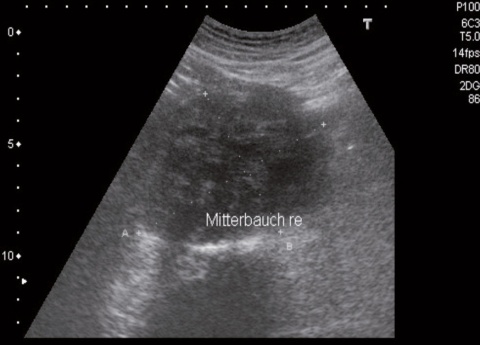

Hier ist zunächst einmal die zu versorgende Patientenklientel zu nennen. Wird in beiden oben genannten Beschreibungen der Allgemeinmedizin von „allen Patienten“ bzw. Menschen „jeden Alters“ gesprochen, finden sich innerhalb der Versorgungsbereiche der (die überwiegend Allgemeinmedizin praktizierenden) Regionalen Sanitätseinrichtungen der Bundeswehr (RegSanEinr) bzw. Behandlungseinrichtungen von Luftwaffe und Marine in der Regel unstrittig keine Kinder und Jugendliche unterhalb des 17. Lebensjahres. Auch Patienten ab dem 65. Lebensjahr gehören bislang nicht zum typischen Versorgungsalltag. Akut- und Notfälle innerhalb des Grundbetriebes (etwa bei Veranstaltungen, Hilfseinsätzen oder bei Besuchergruppen) sowie die allgemeinärztlichen Behandlungen im Zuge der Auslandseinsätze bilden regelmäßige wenn auch nicht repräsentative Ausnahmen. Innerhalb der Alters- und Geschlechterverteilung sind die Häufungen innerhalb des Patientenaltersbandes und des Anteils von Patientinnen variabel. In RegSanEinr mit überwiegender Versorgung von aktiven Truppenteilen wird man jüngere Patienten vorfinden als in Einrichtungen mit „Patientenklientel der Ämterebene“ (siehe Abb. 1).

Der Anteil chronisch erkrankter Soldatinnen und Soldaten innerhalb des allgemeinmedizinischen truppenärztlichen Sprechstundenalltags ist ebenfalls von der Altersverteilung der zugeordneten Betreuungsklientel abhängig. In Anwendung der üblichen Definition (6) liegt der Anteil chronisch Erkrankter und schwerwiegend chronisch Erkrankter innerhalb der allgemeinmedizinischen truppenärztlichen Routinesprechstunde im Sanitätsversorgungszentrum Bonn (zur Altersverteilung des Patientenguts siehe Abb.1) etwa im Häufigkeitsbereich ziviler Allgemeinarztpraxen. Der nicht zuletzt von ziviler Seite immer wieder zu hörenden Einschätzung, ambulant tätige Bundeswehrallgemeinmediziner würden überwiegend „junge und gesunde Patienten“ behandeln, muss angesichts der tatsächlichen Krankheitsverteilung in vielen allgemeinmedizinischen „Bundeswehrpraxen“ deutlich widersprochen werden. Ähnlich differenziert muss die Möglichkeit lebensbegleitender Betreuung von Patientinnen und Patienten bewertet werden: Gerade in Ballungsgebieten mit räumlich enger Anordnung von Bundeswehrkommandobehörden, Ämtern und Dienststellen mit ähnlich hohem Anteil lebensälterer Soldatinnen und Soldaten führen lange Stehzeiten (Phasen ohne Versetzung) von Arzt und Patienten nicht selten zu kontinuierlichen allgemeinmedizinischen truppenärztlichen Betreuungszeiten von deutlich über 15 Jahren. Nicht selten führen die so entwickelten Beziehungen zwischen Truppenarzt und Patient zu teilweise intensiven Kenntnissen über die familiären Verhältnisse der Soldatinnen und Soldaten, wie sie insbesondere in städtischen Allgemeinpraxen längst nicht mehr die Regel sind.